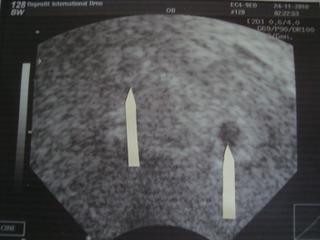

Ahoj všem. tak jsem zpátky od doktorky se špatnýma zprávama 😒 Udělala mi UZ a řekla, že nález neodpovídá prosperujícímu těhotenství a když jsem se jí přímo zeptala, jestli je z toho ještě nějaká jiskřička naděje, tak prý asi ne. Prý by bylo lepší to ukončit a raději se soustředit na další pokus 😒 Nabrala mi krev, léky zatím nevysazovat a v pondělí na kontrolu. Je mi z toho smutno.............bohužel tady se potvrzuje že // ještě zdaleka neznamenají výhru 😒